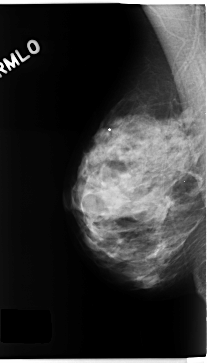

C_0272_1.LEFT_MLO

LEFT_MLO LINES 4560 PIXELS_PER_LINE 2992 BITS_PER_PIXEL 12 RESOLUTION 50 OVERLAY

RIGHT_MLO LINES 4712 PIXELS_PER_LINE 2688 BITS_PER_PIXEL 12 RESOLUTION 50 NON_OVERLAY